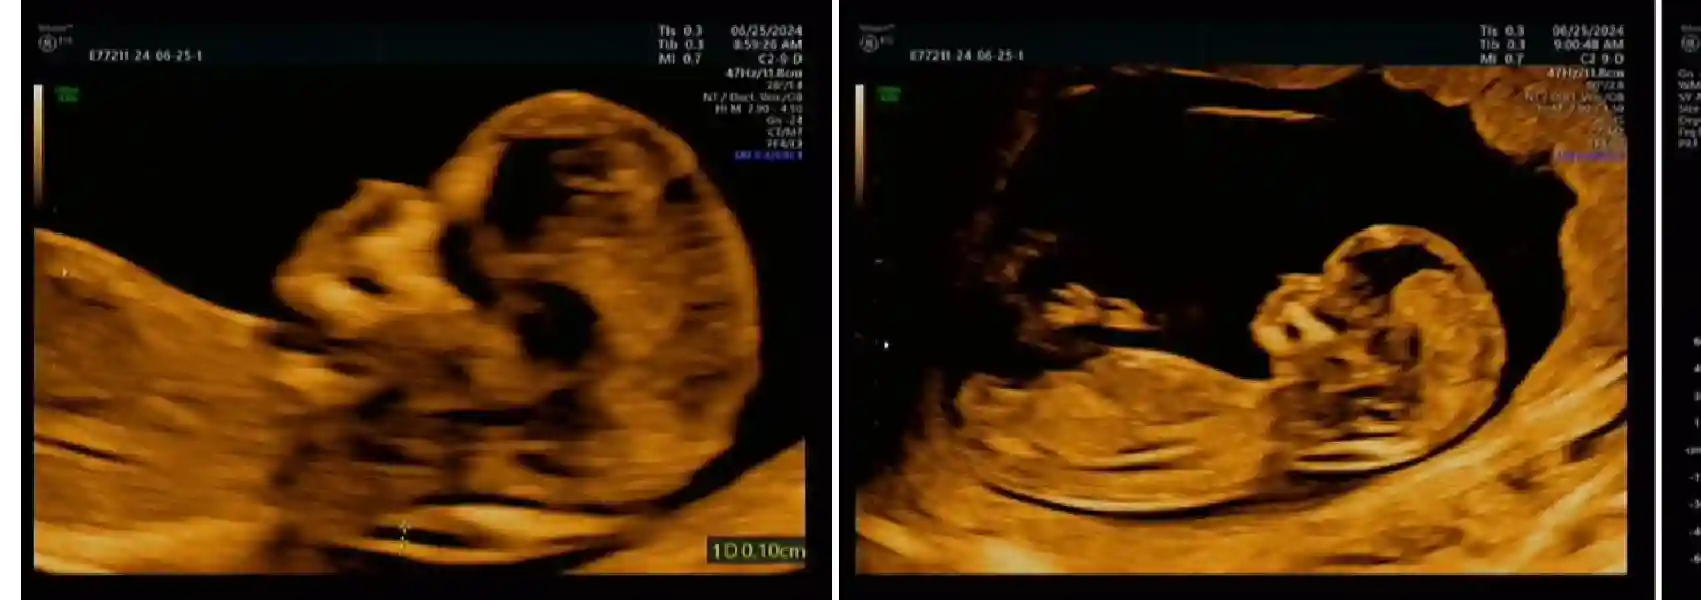

再简单聊一下徐州云龙区建档吧 我们是属于东苑社区医院的 周一到周六早上八点就可以排队挂号-妇科 把近期检查过的报告给医生 她会根据内容再做调整 有免费也有需要自费的 居民医保也是可以报销的 我和我老公早上空腹去的 没什么人 花费大概是900左右(报销后) 会填一些信息 夫妻双方也有个电子照采集 抽血的话我只抽了四管 没有别人说的十几管子那么吓人 我老公还觉得抽太少了😂被我一记白眼扫过 等检查报告大约需要两三天 应该不是在这个医院检测的 报告上写的是南京某检测中心 报告出来后会打电话联系你 就可以来医院领本子啦 以后每次产检带着小本子就好了~ 哦对 因为我一直服用甲状腺药物 所以橙色高危孕妇 今天是在妇幼做了NT 真的没有其他人说的这么复杂 很简单 一把过 NT需要提前预约哈 不需要空腹 好好吃饭 耿主任看了报告说没问题 接下来就需要去产科报道啦 生殖科已毕业🙏🏻